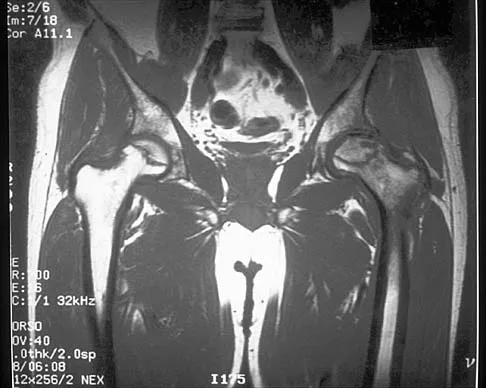

Question 57

Figure 41 shows the MRI scan of a 39-year-old man who has severe left groin and anterior thigh pain. What is the most likely diagnosis?

Explanation